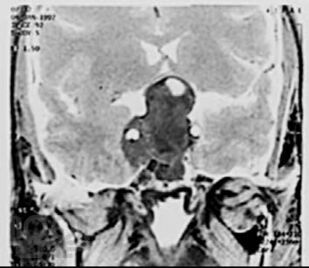

Первичные опухоли головного мозга

Кратко изложены этиология, особенности эпидемиологии, патогенеза, классификация и основные клинические проявления первичных опухолей головного мозга, современные принципы клиники, диагностики и оказания госпитальной помощи больным с данной патологией. Представлены алгоритмы обследования и лечения больных с наиболее часто встречающимися опухолями в зависимости от стадии течения патологического процесса.